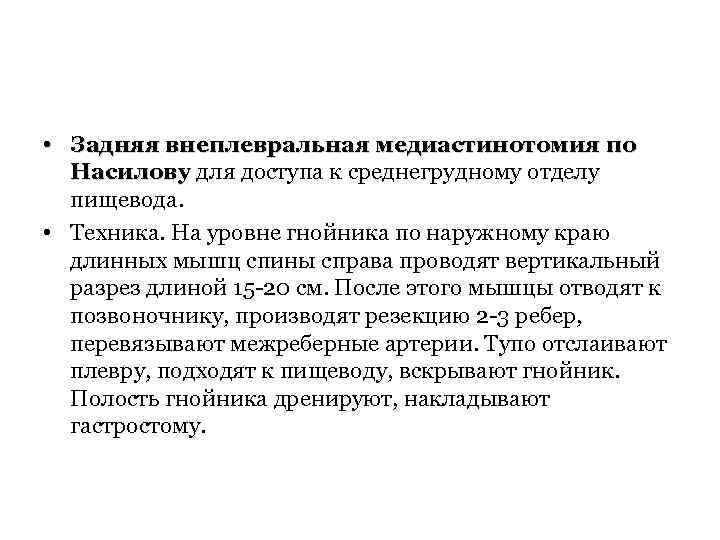

• Задняя внеплевральная медиастинотомия по Насилову для доступа к среднегрудному отделу пищевода. • Техника. На уровне гнойника по наружному краю длинных мышц спины справа проводят вертикальный разрез длиной 15 -20 см. После этого мышцы отводят к позвоночнику, производят резекцию 2 -3 ребер, перевязывают межреберные артерии. Тупо отслаивают плевру, подходят к пищеводу, вскрывают гнойник. Полость гнойника дренируют, накладывают гастростому.

• Задняя внеплевральная медиастинотомия по Насилову для доступа к среднегрудному отделу пищевода. • Техника. На уровне гнойника по наружному краю длинных мышц спины справа проводят вертикальный разрез длиной 15 -20 см. После этого мышцы отводят к позвоночнику, производят резекцию 2 -3 ребер, перевязывают межреберные артерии. Тупо отслаивают плевру, подходят к пищеводу, вскрывают гнойник. Полость гнойника дренируют, накладывают гастростому.